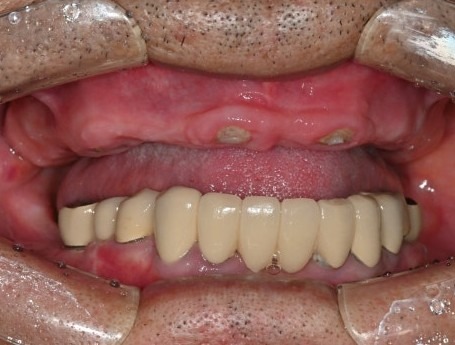

CT 분석을 통해 틀니가 아닌

고정성 임시치아가 가능하다고 말씀을 드리자

임플란트로 치료 계획을 결정하셨습니다.

수술 후

8개의 전체임플란트를

하루에 바로 수술할 수 있었고,

병원 내의 디지털기공소에서

바로 임시치아를 제작하였습니다.

수술 전

수술 1일 후

하루만에 위턱 전체 치아가 생겨서

식사가 바로 가능하시게 되자

환자분은 너무 놀라워하시고 좋아하셨습니다.